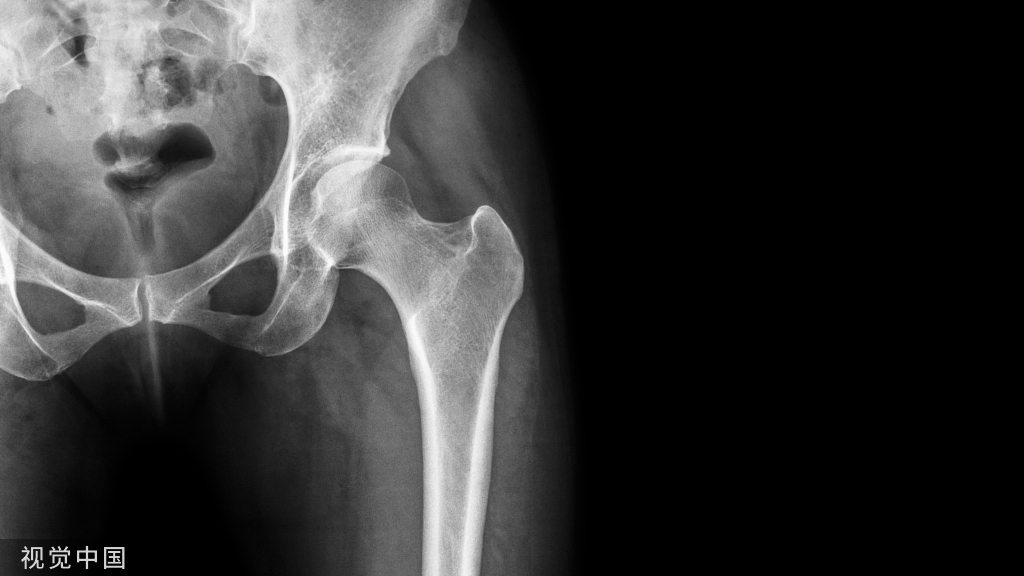

影像学检查:CBCT矢状面、冠状面示37根充糊剂进入下颌管患者。

CBCT示37根充糊剂进入下颌管

CBCT矢状面、冠状面示37根充糊剂进入下颌管